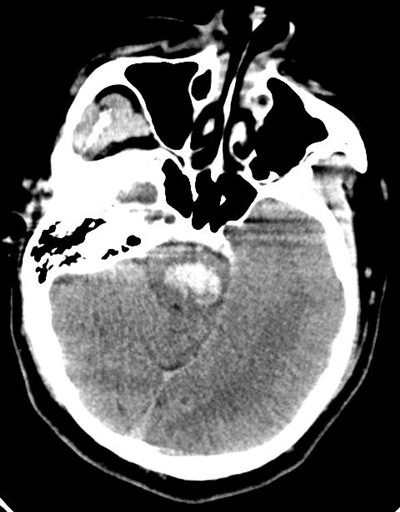

术后20天,脑干出血患者可以站起来,出院了

5月6日,20天前因脑干出血就诊北医三院的患者程先生,可以站起来,出院了。 2019年4月16日中午,行色匆匆的神经外科副主任医师孙建军赶到急诊抢救室,会诊一位脑干出血的患者。这位41岁的男性患者已经昏迷、偏瘫、生...